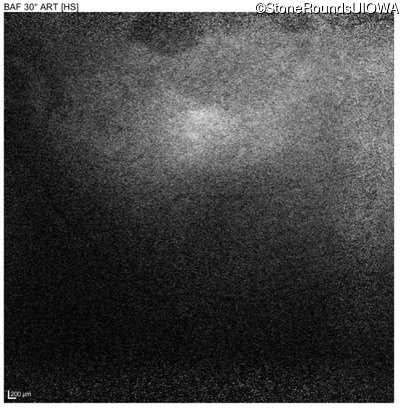

Blue Autofluorescence - Right - 10/300 sc

Exemplar